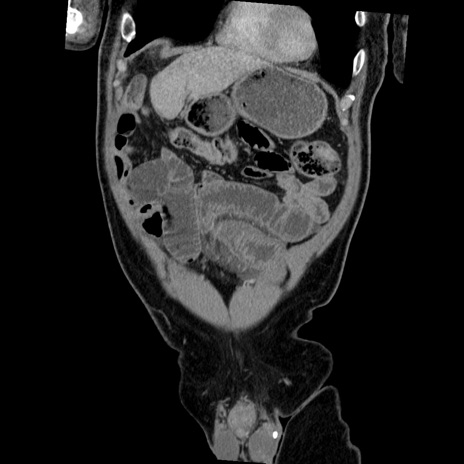

症例22(冠状断像)

【症例】50歳代男性

【主訴】腹痛

【現病歴】AVMからの被殻出血のため回復期リハ病棟入院中。 本日午後3時頃急に下腹部痛が出現した。

【既往歴】AVM、被殻出血、虫垂炎、高血圧

【身体所見】意識晴明、左半身不全麻痺、会話の理解は良好、36.5°C、腹部:膨隆、全体に板状硬、下腹部正中に圧痛点あり、反跳痛-、筋性防御不明、右下腹部にope scar

【データ】WBC 9400、CRP 0.06